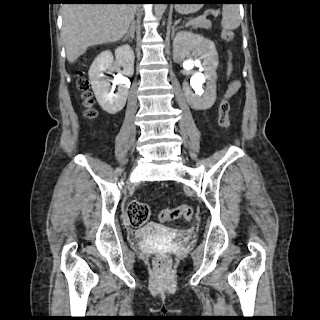

Deleted 30 Min CT images

A 50 years old woman with suffering from left sided PUJ obstruction